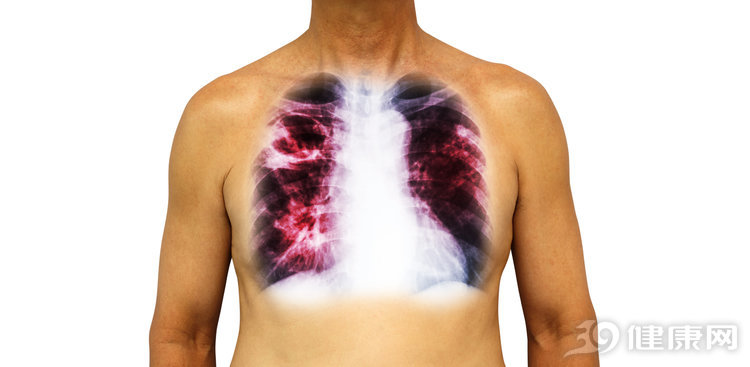

另外,需要強調的是,肺結核為通過唾液傳播的疾病,因此如果與肺結核患者一起吃飯又不注意保護好自己,如果患者病情處於活動期,那麼感染肺結核的幾率是很大的,但是並不是所有肺結核患者就一定具有強傳染性,只有處於活動期的患者,才具有傳染性。